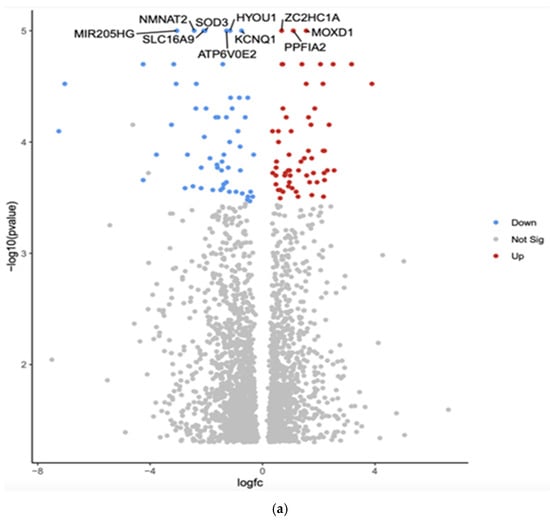

Unraveling Racial Disparities in Papillary Thyroid Cancer: A Comparative Bulk RNA-Sequencing Gene Expression Analysis

Curr. Oncol. 2025, 32(6), 315; https://doi.org/10.3390/curroncol32060315 - 29 May 2025

Papillary thyroid cancer (PTC) is the most common thyroid malignancy, with significant racial/ethnic disparities in incidence and survival. Asians have the highest incidence, and recurrence, while African Americans experience the lowest survival rates, suggesting contributions from genetic, environmental, and healthcare-related factors. While socioeconomic

[...] Read more.

Papillary thyroid cancer (PTC) is the most common thyroid malignancy, with significant racial/ethnic disparities in incidence and survival. Asians have the highest incidence, and recurrence, while African Americans experience the lowest survival rates, suggesting contributions from genetic, environmental, and healthcare-related factors. While socioeconomic disparities play a role, emerging evidence highlights genetic and molecular mechanisms underlying these differences. This study examines differentially expressed genes (DEGs) to identify potential molecular drivers of PTC disparities. Bulk RNA-sequencing (RNA-seq) data from 20 PTC tumors (5 White, 5 African American, 5 Hispanic, and 5 Asian) were analyzed using the UseGalaxy platform. Preprocessing included quality control, adapter trimming, and genome alignment. Differential expression analysis identified genes with p < 0.01 and fold change ≥ 2.5. Volcano plots visualized significant DEGs. Gene Set Enrichment Analysis (GSEA) via eVITTA identified enriched pathways. TCGA data analysis validated racial/ethnic differences in gene expression. Ethnic groups exhibited distinct gene expression profiles. GSEA revealed differences in cell proliferation, immune regulation, and thyroid hormone metabolism. African Americans showed immune suppression and reduced tumor suppressor activity, while Asians exhibited enriched cell cycle and DNA repair pathways. Significant differences were confirmed in some of the genes in TCGA data analysis. This study identifies genetic factors contributing to racial disparities in PTC, emphasizing the need for further validation in larger cohorts and functional studies. Understanding these molecular differences may inform personalized treatment strategies and improve PTC outcomes across diverse populations.